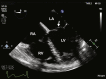

Traumatic Injury to Both Atrioventricular Valves

Keywords: Atrioventricular valve injury; Blunt cardiac injury; Echocardiography; Traumatic mitral regurgitation; Traumatic tricuspid regurgitation.